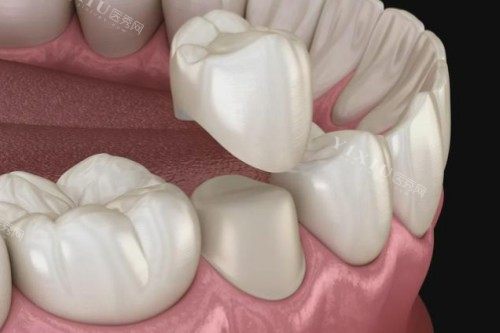

在选择镶牙材料的时候,医生没有像有些地方那样一个劲儿地推荐贵的,而是根据我的实际情况,给我推荐了性价比比较高的材料。他说镶牙不是越贵就越好,适合自己的才是更重要的。我听着觉得挺在理,就按照他的建议选了材料。

确定好方案后,就开始镶牙了。整个过程中,医生和护士配合得相当默契。医生的手法很娴熟,动作也很轻柔,一点都没有让我感觉到特别疼。遇到可能会有点不舒服的步骤,护士还会握着我的手安慰我,让我放松。说实话,我原本心里还挺紧张的,但在他们的安抚下,我慢慢就不那么害怕了。